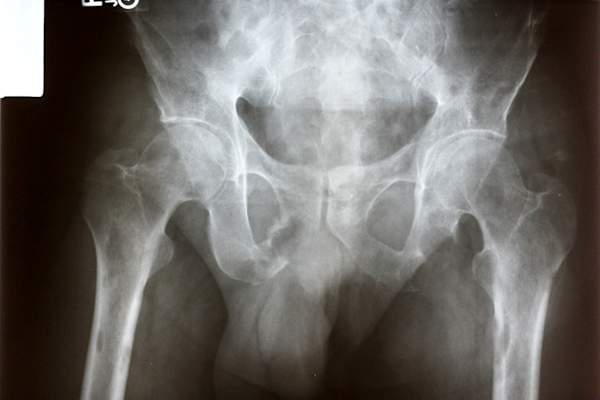

骨转移的风险

超过一半的4期乳腺癌患者经历过骨转移据breastcancer.org网站报道。通常,乳腺癌扩散的第一个部位是骨骼,最常见的受影响部位包括肋骨、脊柱、骨盆、胳膊和腿骨。如果你怀疑癌症已经扩散到骨头上,尽快检查是很重要的,因为及时治疗可以防止骨折。

骨转移的迹象

注意突然出现的新疼痛,特别是休息或躺下后还没有消失的疼痛。其他症状包括:

- 不能移动(可能是骨折)

- 任何部位的麻木或无力

- 便秘

警觉性下降、疲劳、虚弱、恶心、食欲不振和脱水都可能是由于骨骼分解导致血液中钙含量上升的迹象。

- 全身骨扫描